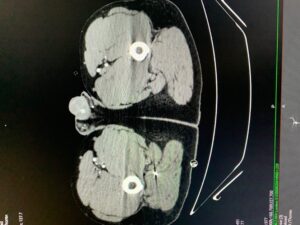

Over the last 3,000 years, combat has certainly changed, with a Trojan horse now referring to a method of electronic warfare rather than the legendary wooden decoy, however soldiers continue to experience peripheral nerve trauma from extremities that are not protected by modern body armor. While deployed I evaluated two patients injured in a 107mm Katyusha rocket attack who each sustained fragmentation injuries to the extremities (Figure 1 and 2). One patient had a large entrance wound in the right buttock with the fragment passing just posterior and lateral to the sciatic nerve, which could be palpated through the wound itself. The nerve was inspected and neurolysed, with only minor bruising present, and the patient maintained full function of the lower extremity. The other patient was injured in the same rocket strike, holding up his arms in a blocking fashion and had several fragments lodged in his upper extremities, the largest of which was removed from his forearm. Thankfully no nerve injuries were identified.